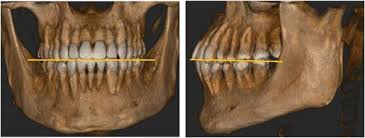

The Prevalence And Distribution Of Radiopaque Calcified Pulp Stones A Cone Beam Computed Tomography Study In A Northern Taiwanese Population Sciencedirect